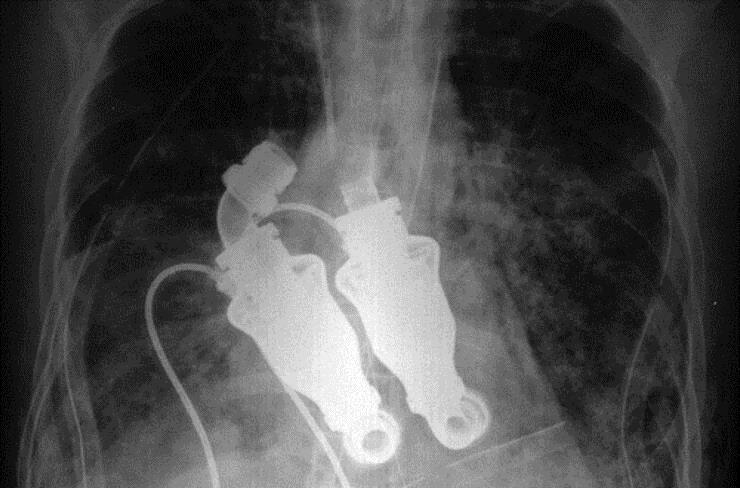

当刘易斯进入医院的时候 , 他的心脏已经彻底报废 , 他将在接下来的 12 到 24 小时内死亡 。 对刘易斯来说幸运的是 , 比利·科恩(Billy Cohn)和巴德·弗朗茨(Bud Frazier)两位医生都没有准备放弃他 , 这两位医生都来自美国德克萨斯心脏研究所 , 它们一生的大部分时间都在开发替代或修复人类心脏的技术 。 他们制造了一种他们称之为“连续流”的机器 。 可以通过让血液“连续流动”有效地使人类在没有脉搏和心跳的情况下存活下来 。 这个“离心泵”一样的装置有点像是一台涡扇 , 装有简单的转子结构 。 这台装置并不会像心脏那样跳动 , 其目标是像花园里的浇水管一样提供“连续不断的血流” 。

他们之前在50头小牛身上进行了实验 , 将它们的整个心脏取出 , 并用这台机器取而代之 , 都取得了成功 , 所以他们做了一些激进的事情 , 他们取出了刘易斯的心脏并用他们自己制造的机器充当刘易斯的心脏 。

安装成功之后 , 刘易斯的心电图成了一条直线 , 但刘易斯还活着并且正常 。 当科恩博士将听诊器放在刘易斯的胸前时 , 他没有听到心跳声 , 而是嗡嗡声 。

在手术之前 , 刘易斯一直在透析机上 , 处于昏迷状态 。 但手术后 , 他能够坐下来和每个人交谈 。 克雷格·刘易斯先生成为世界上第一个没有心脏的人 。

第二天医生走进来 , 刘易斯已经可以在他的电脑上写作和工作 。 没有脉搏和心跳 , 并没有对刘易斯产生什么影响 。

这项实验最大的意义 , 就是证明了没有脉搏也可以支持人体生理机能 。 要知道如果按照传统的医学分析方法 , 刘易斯已经没有心跳 , 因而已经死亡了 。